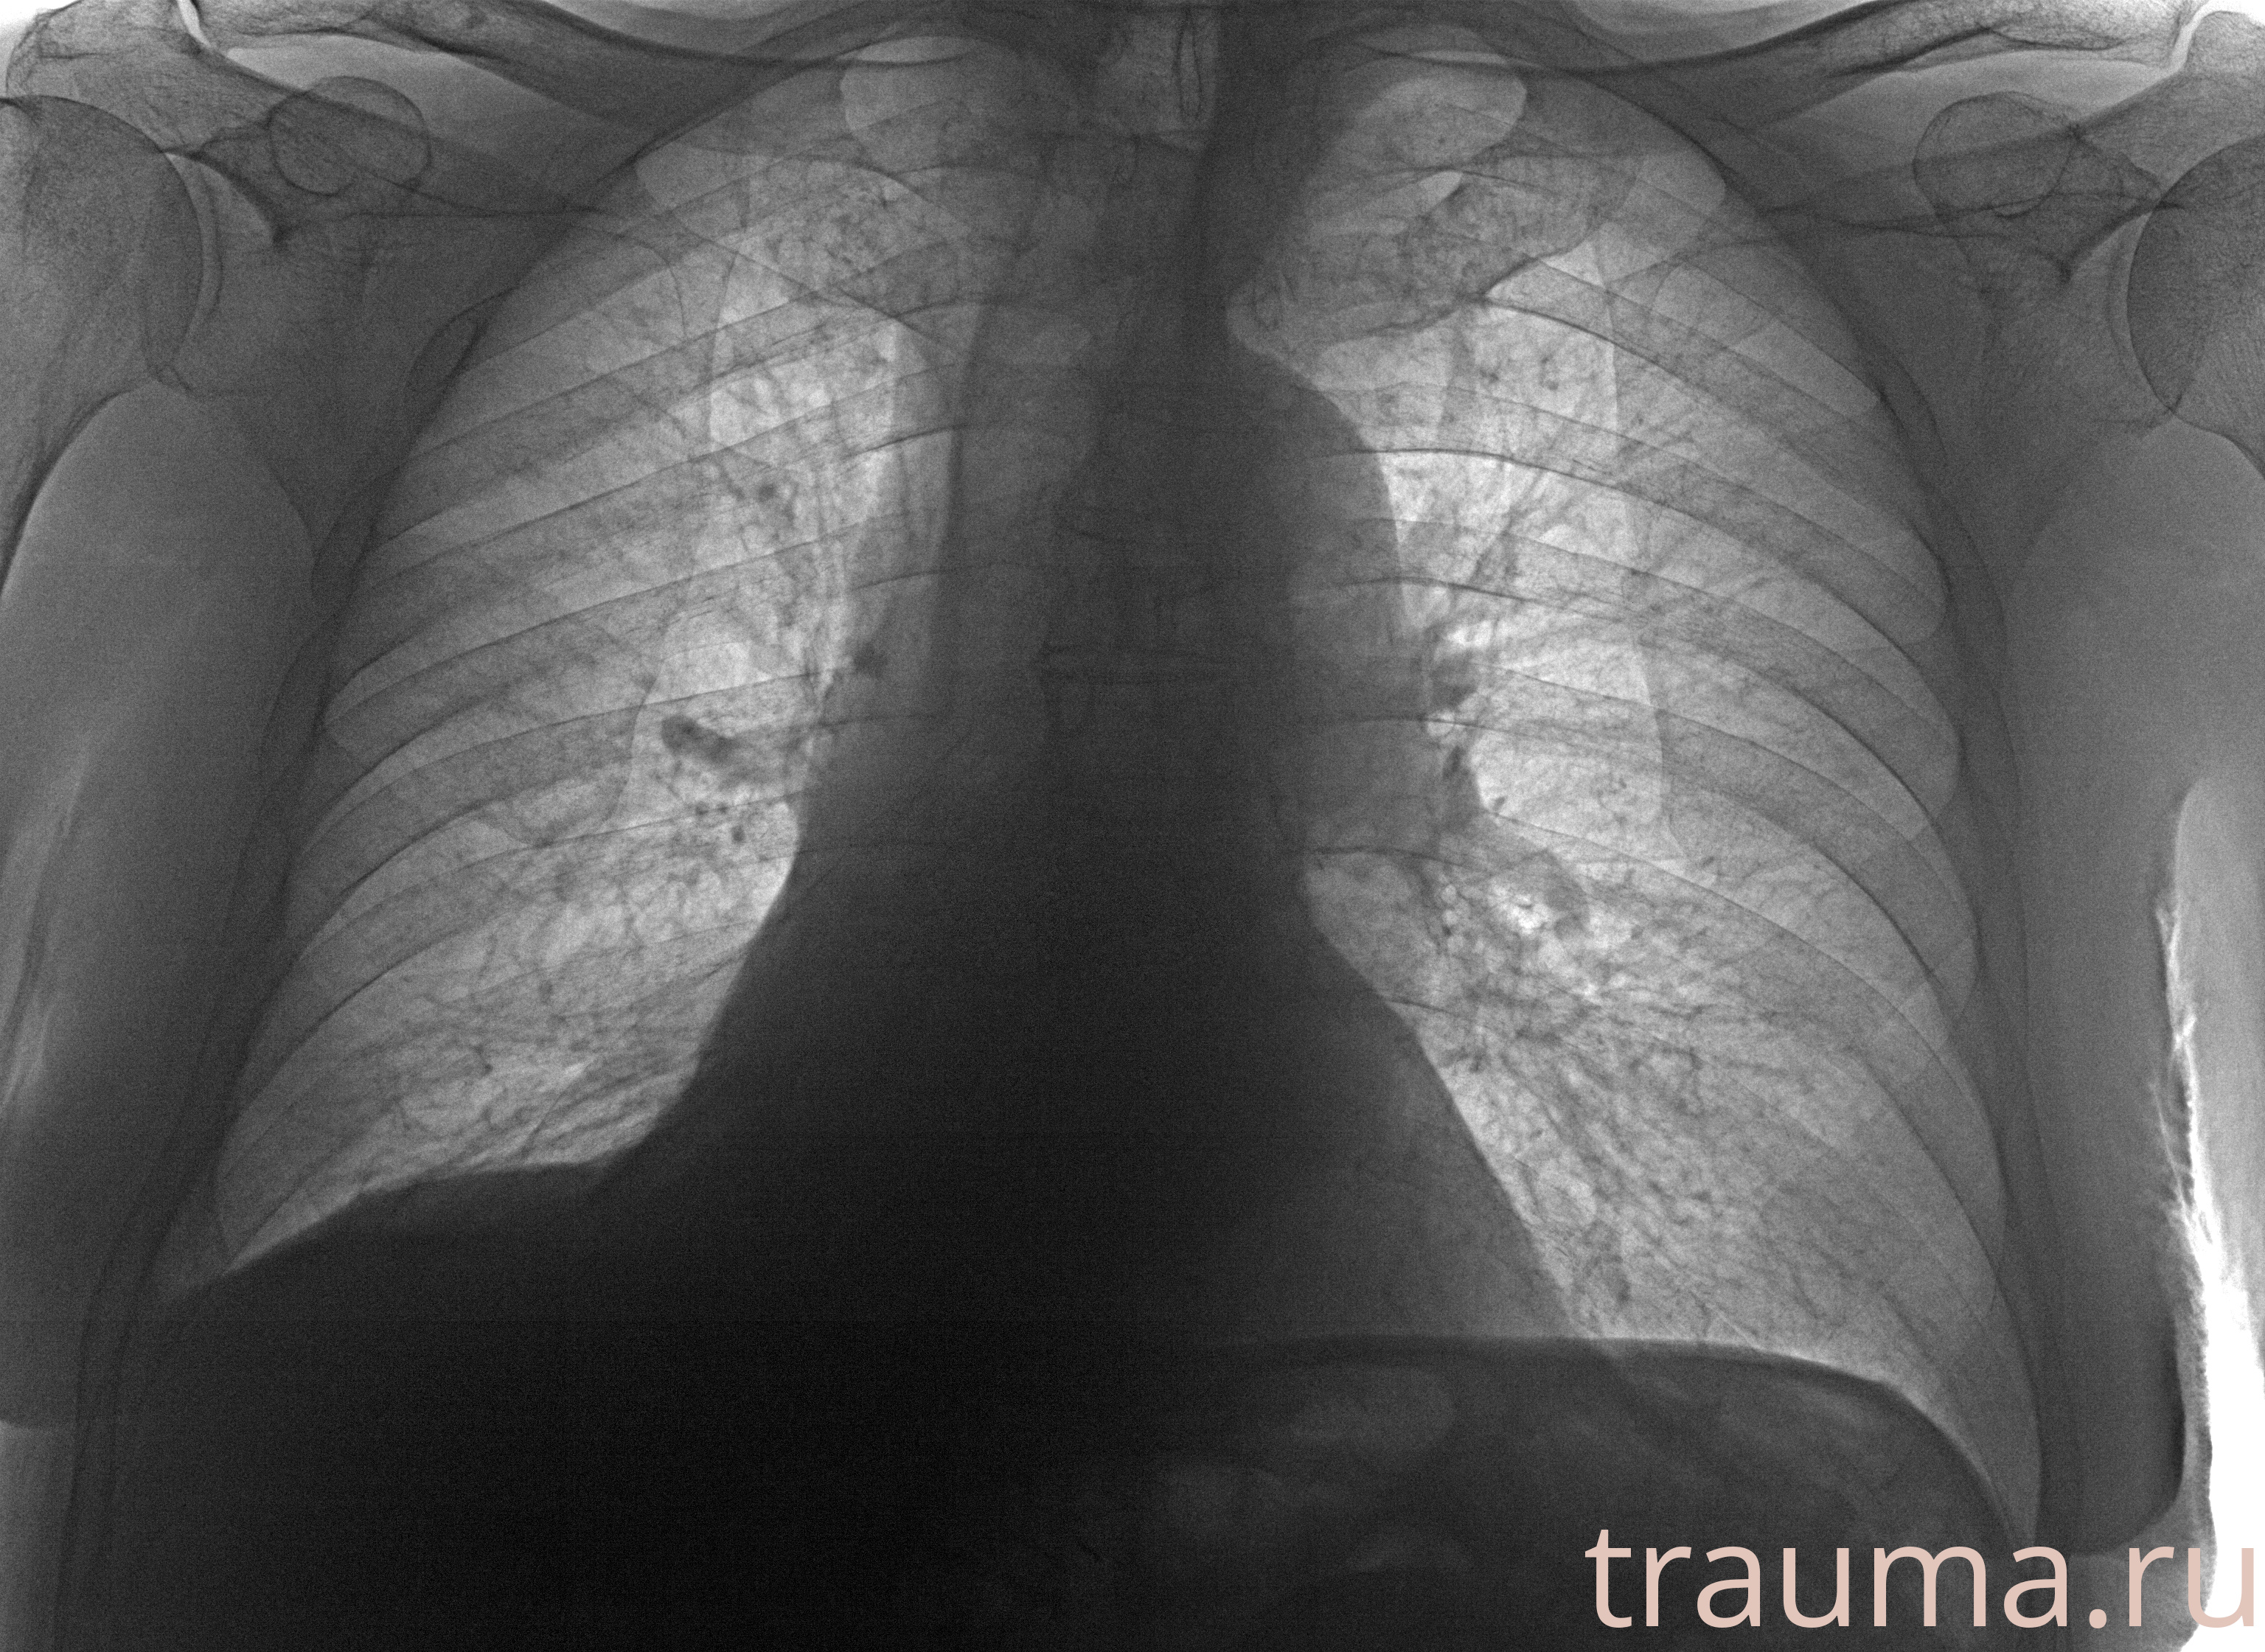

Рентгенограммы

Рентген на дому: по вашему адресу приезжает врач-рентгенолог, травматолог-ортопед с мобильным рентгеновским аппаратом, проводит диагностику травмы или заболевания, делает необходимые рентгенограммы, дает рекомендации по дальнейшему лечению. Получить качественные снимки в домашних условиях возможно благодаря уникальной методике, разработанной МосРентген Центром для института  Склифосовского